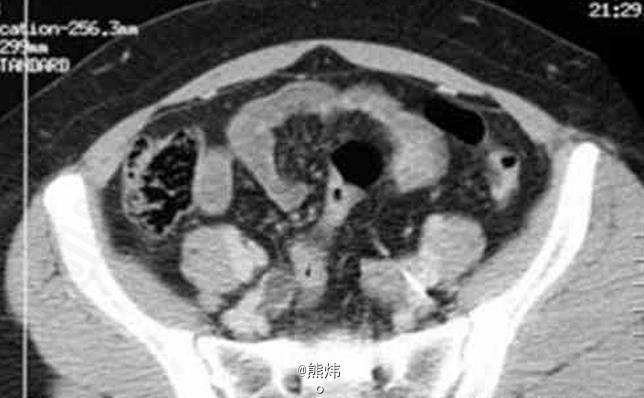

临床一例肾结核

肾结核

患者 女 30岁,因右腰疼痛1年前来就诊,既往无临床病史。

查:镜下血尿,尿培养阴性。伴有腰痛和发热 辅查造影

肾结核 处理:积极抗结核处理,采用链霉素